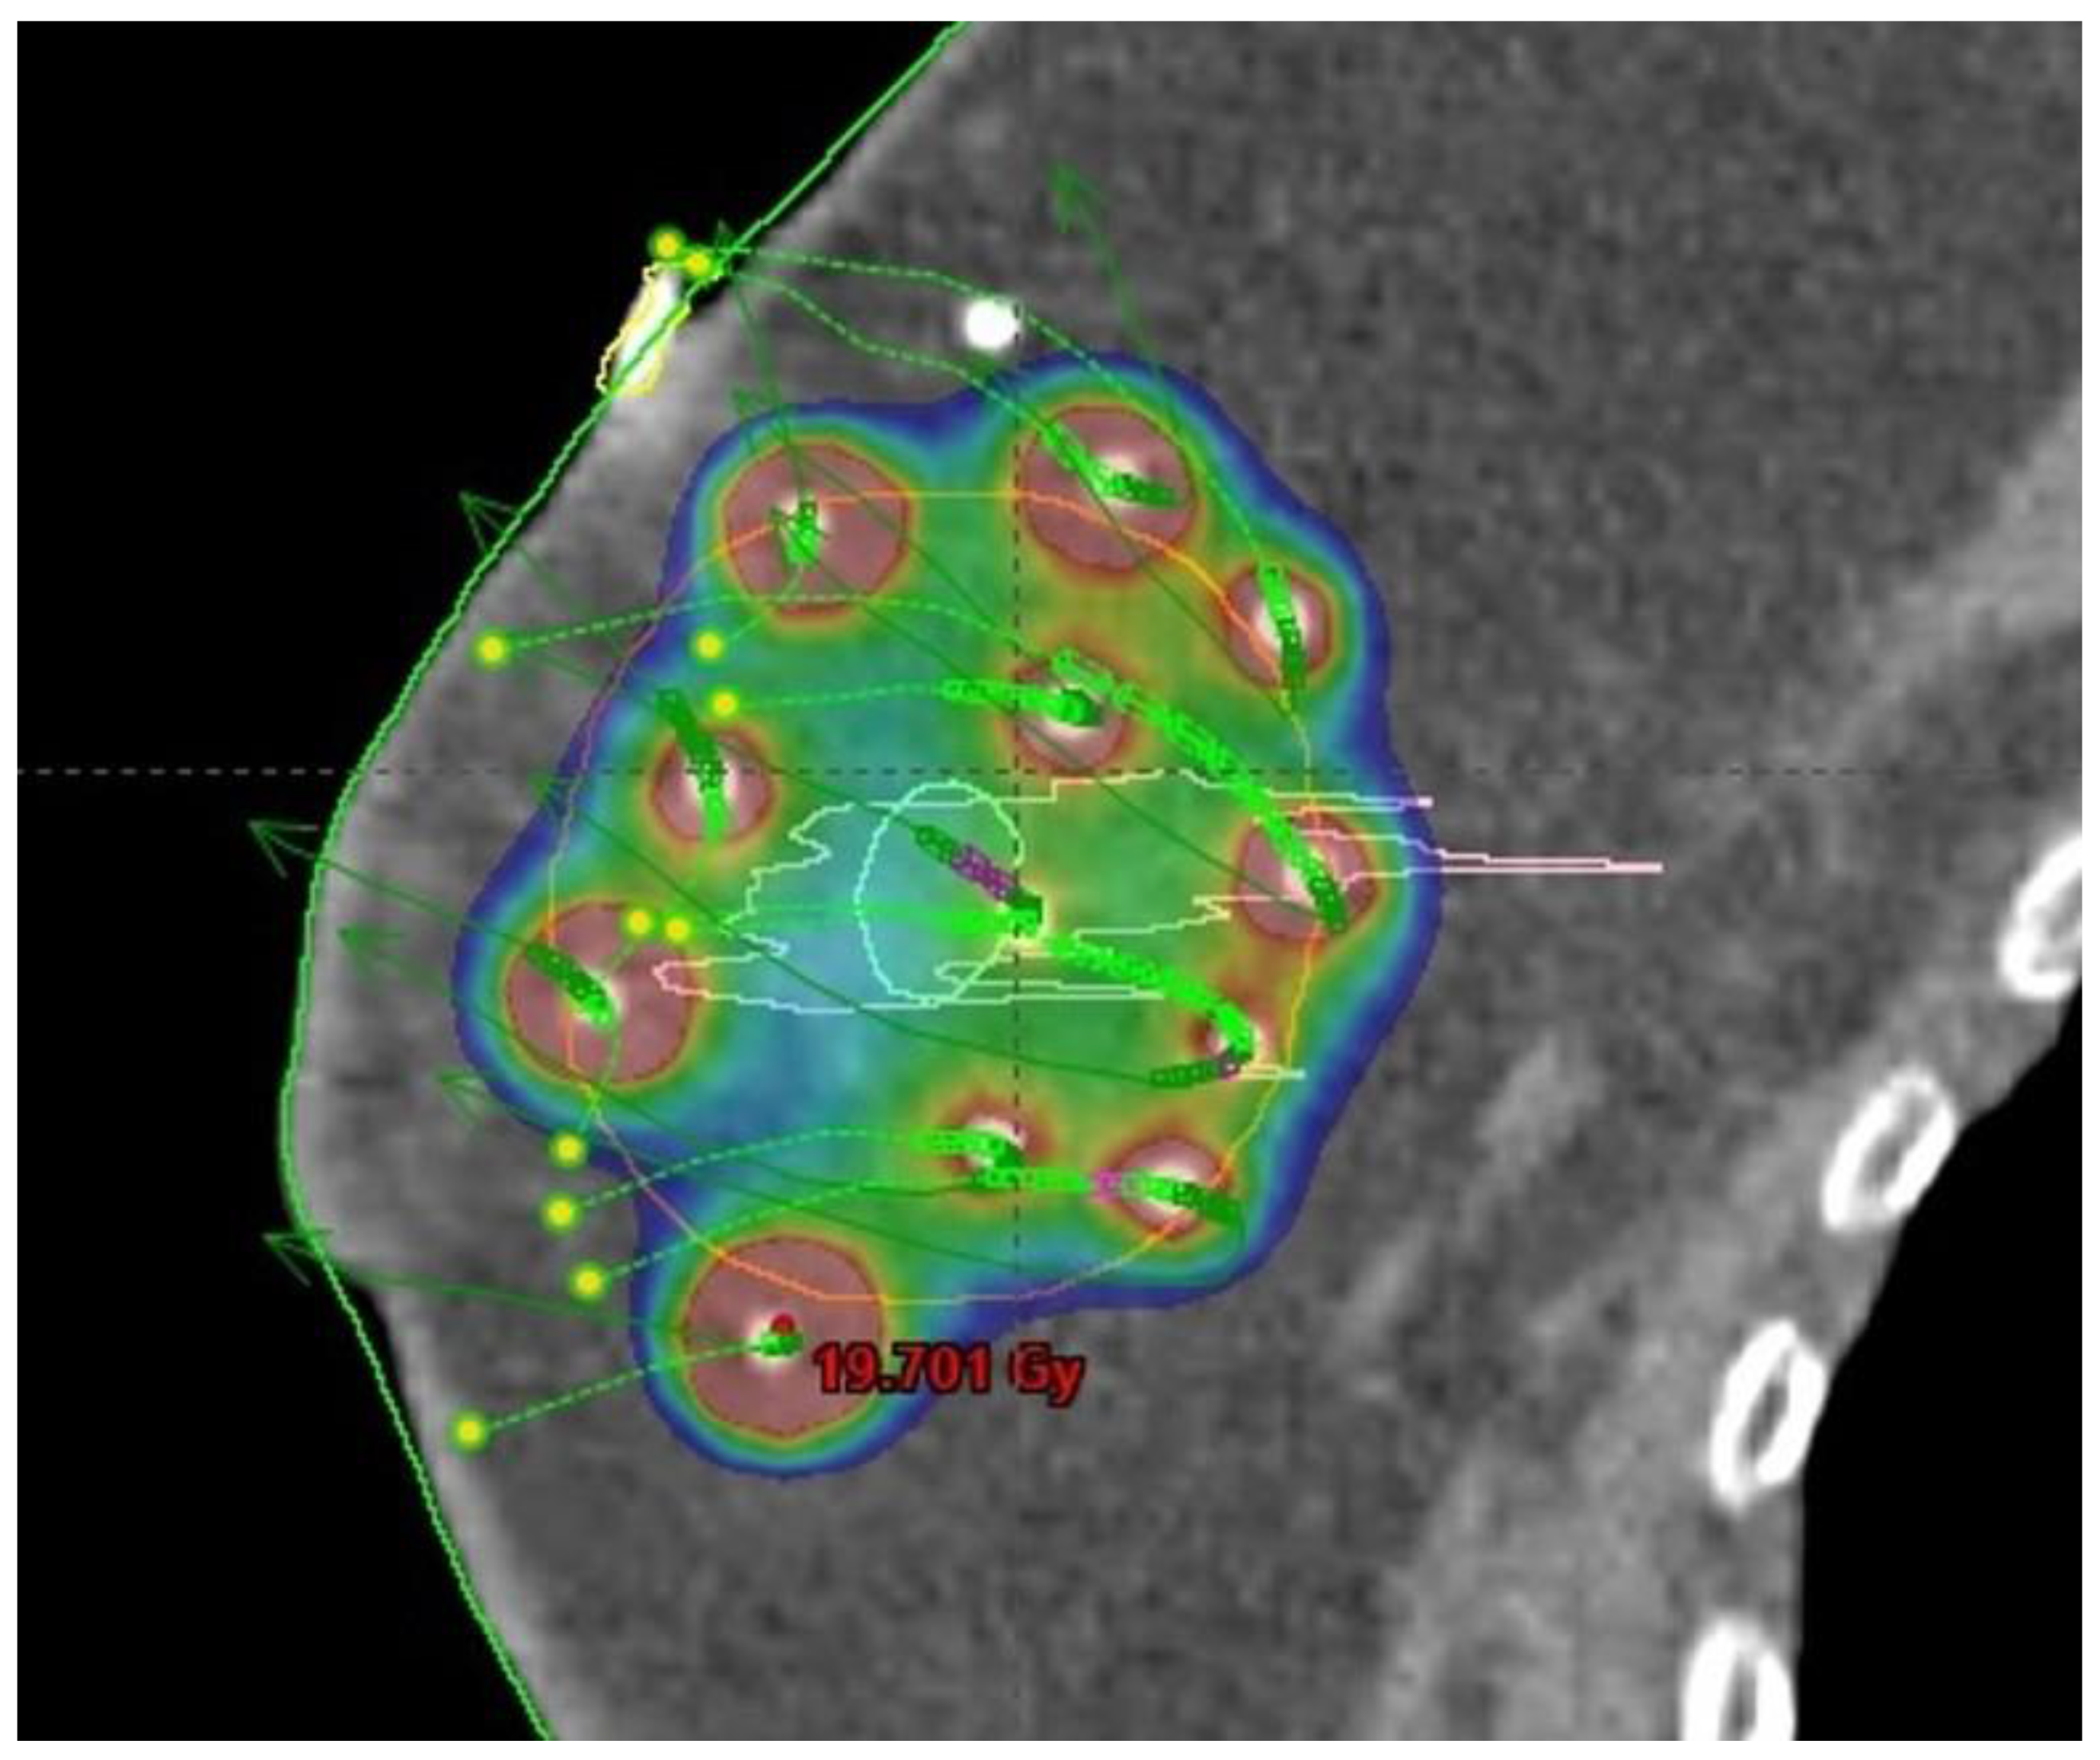

Figure 4. Multicatheter interstitial accelerated partial breast irradiation (APBI): prescribed dose distribution.

The use of breast-conserving surgery is also supported by the availability of the option to modify adjuvant breast irradiation that would further decrease the side effects of therapy compared to WBI. Selected subgroups of patients can be treated with less extensive radiotherapy techniques including accelerated partial breast irradiation (APBI, Figure 4), partial breast irradiation (PBI, Figure 3), or intraoperative radiotherapy (IORT) [22].